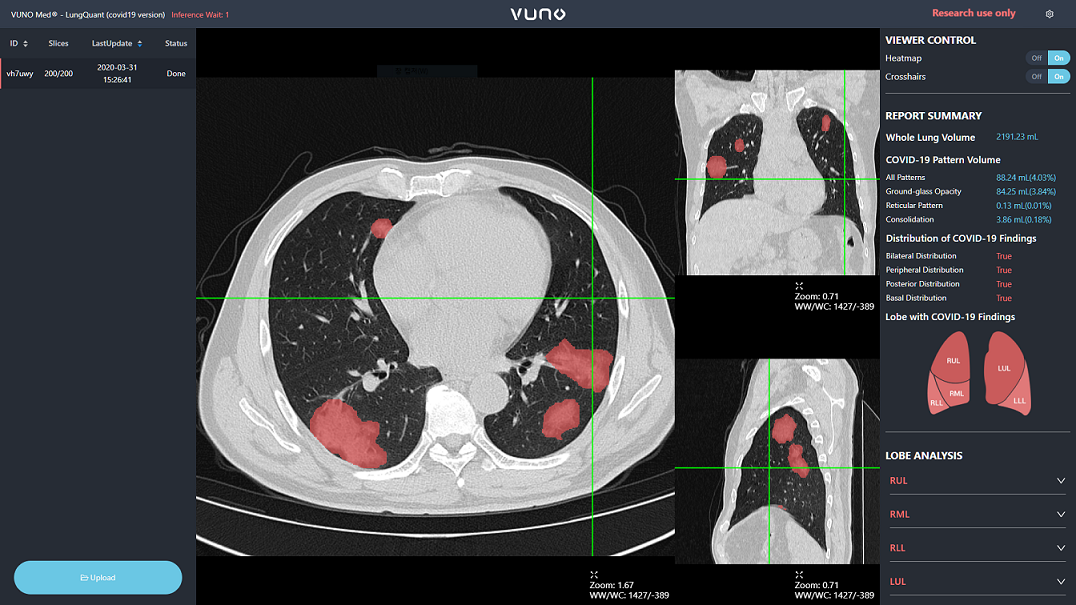

이번에 공개되는 ▲뷰노메드 렁퀀트(VUNO Med-LungQuant) ▲뷰노메드 체스트 엑스레이-코로나19 버전(VUNO Med-Chest X-ray: COVID-19 Version)은 클라우드 기반 웹 서비스다. 전 세계 어디에서나 실시간으로 활용할 수 있다.

뷰노메드 렁퀀트는 1분 내로 코로나19 소견에 해당하는 병변의 분포와 부피 정보를 제공해 의료진의 신속한 진단을 보조한다. 특히, 코로나19 폐렴 환자의 CT내 주요 소견인 ▲간유리 음영(Ground Glass Opacity, GGO), ▲망상음영(Reticular Opacity), ▲경화(Consolidation)를 탐지할 수 있다.

또 관련 리포트를 사용자 중심 인터페이스로 시각화해 의료진이 환자의 상태와 경과를 보다 간편하게 파악할 수 있도록 했다.